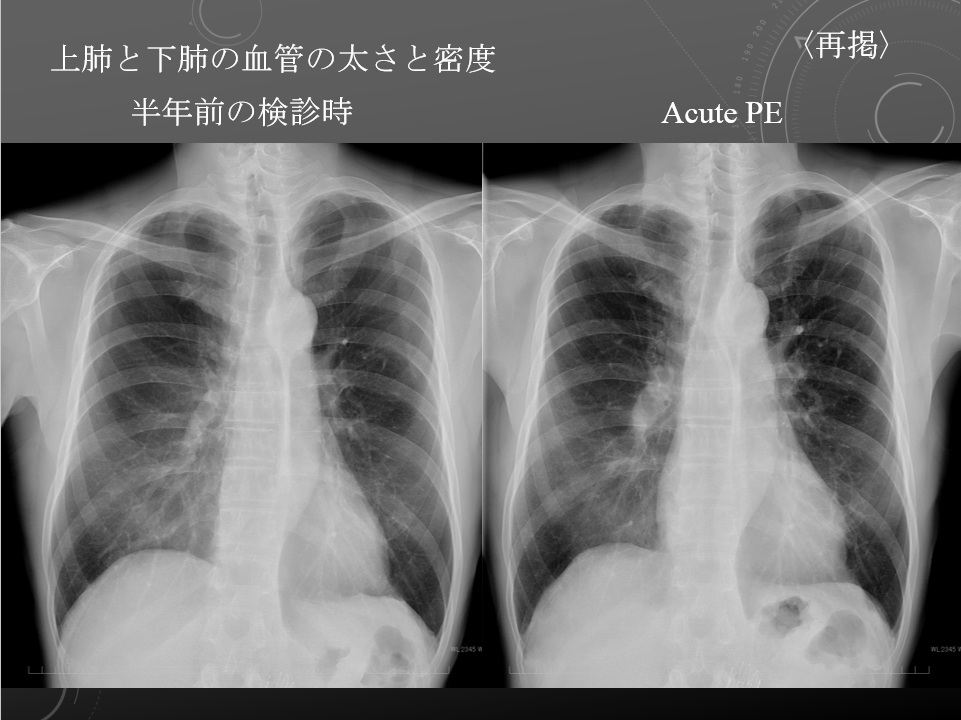

2週間前犬の散歩中に突然の呼吸苦、乾性咳嗽出現。近医受診、鎮咳薬で経過観察。この際不整脈(?)を指摘。その後も乾性咳嗽が持続するため当院受診。外来待合室で呼吸苦出現。SpO2 77% (ambient air)。

右心系の拡大もあるのか…

肺静脈の狭小化あり

右心系の拡大もあるのかも。。。